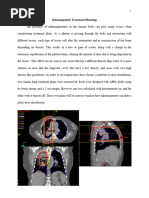

Meanwhile, the same patient and plan is calculated with inhomogeneity correction. The

weighting of the beams has actually been changed to achieve the same dose homogeneity as

before – but differences can be seen between this plan and the plan without any heterogeneity

correction. The isodose lines are bowing in centrally through the treated volume, producing an

hourglass shape, which is a classic dose distribution for this beam and density scenario. This can

be seen clearly in the plan overview below.

This hourglass shape is produced from the reduction of lateral scatter back to the central axis as

the beam traverses low density material – i.e. the lung. The plan is still normalized at the

isocenter, which lies at the center of the tumor volume, and the 100% isodose line still runs

through this point. However, compared to the plan without heterogeneity correction, the 100%

isodose line does not extend into the lung tissue at all.

This distribution is a more accurate representation of what is really happening in low density

tissue – the range of the electrons are increased and there are less interactions and dose

deposition occurring. The secondary build-up effect mentioned earlier can be seen as the 95%

isodose line only just covers the periphery of the tumor, compared to the earlier plan, where it

extends throughout the entire treated volume. Even the effect of higher density materials can be

visualized on the plan that accounts for density changes. At the medial beam edge, the 100% and

30% isodose lines bow away slightly more from the spinal cord than is evident in the bulk-

homogeneity plan. This is because of the increased attenuation of the beam as it traverses bone –

the vertebra posteriorly, and the sternum anteriorly.